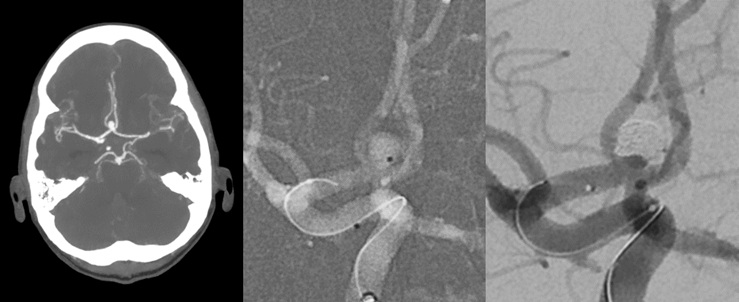

Minimal-invasive Behandlung von Hirnarterienaneurysmen am Klinikum Aschaffenburg

13. Juni 2023 - Seit Anfang 2023 ist PD Dr. Volker Maus als Chefarzt am Klinikum Aschaffenburg tätig und hat seine umfangreiche Expertise im Bereich der interventionellen Neuroradiologie in das Klinikum eingebracht. Bereits im Juni 2023 konnte unter seiner Verantwortung erstmals eine endovaskuläre Behandlung eines Hirnarterienaneurysmas erfolgreich durchgeführt werden. PD Dr. Maus ist zudem DeGIR-zertifiziert und erfüllt damit höchste Qualitäts- und Qualifikationsstandards für minimalinvasive gefäßmedizinische Eingriffe. Weiterlesen